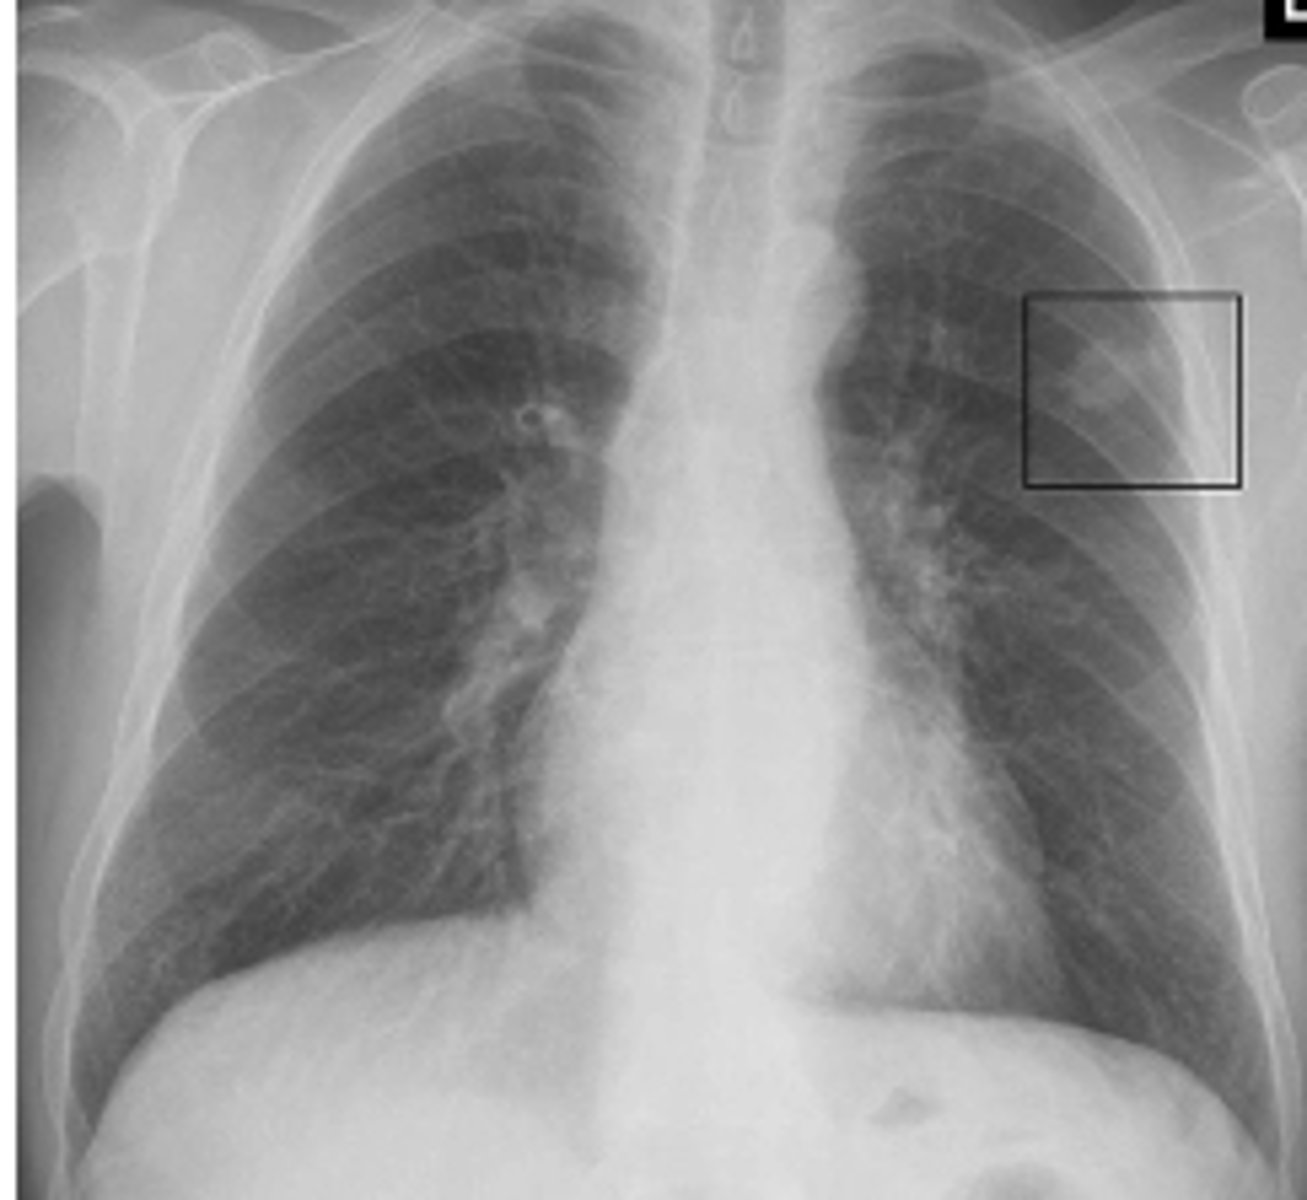

ID Ghon and Ranke complexes on xray

There is a combination of a calcified peripheral granuloma (black arrow) and a calcified hilar lymph node (white arrow) on the same side. Several other, small calcified granulomas are seen in the right mid-lung field - ranke complex

ranke typically more dense

<p>There is a combination of a calcified peripheral granuloma (black arrow) and a calcified hilar lymph node (white arrow) on the same side. Several other, small calcified granulomas are seen in the right mid-lung field - ranke complex</p><p>ranke typically more dense</p>